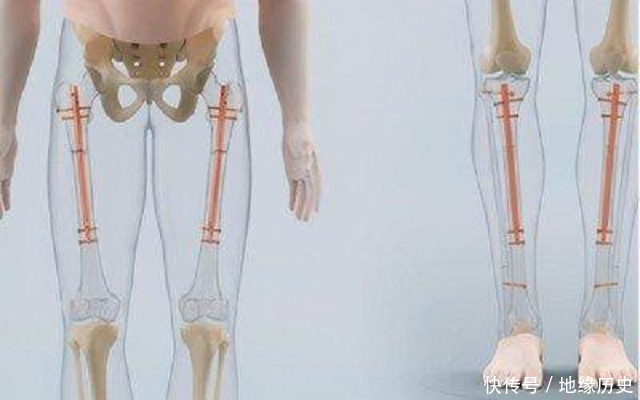

他评释注解着:“便是将腿骨打断,用东说念主工打造钢板的阵势把腿骨重新接起来,通盘东说念主就不错增高。”

据大夫先容,这项手术在国内属于前沿,许多医疗整形病院还不敢奢靡,是以他购买的用具药材齐是来自海外,所有耗尽10万元之多,再加上手术流程中的麻醉、药物以及术后照看,还要6万多块钱。